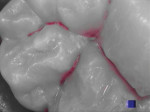

SoproCARE has three unique modes—Daylight, Cario, and Perio (Figure 1 and Figure 2). When used in this order, a predictable clinical protocol is developed that, with proper training, can be implemented by general practitioners and other members of the dental team during the prophylaxis appointment.

Perio mode utilizes SoproCARE’s blue and white light to detect oral biofilm and any tissue inflammation (Figure 2). Biofilm is displayed as white for newer plaque and yellow or orange for older plaque. Inflammation of the gingiva can range from pink to deep magenta. The camera can connect to any image management program, making it easy to integrate results into a patient’s chart.